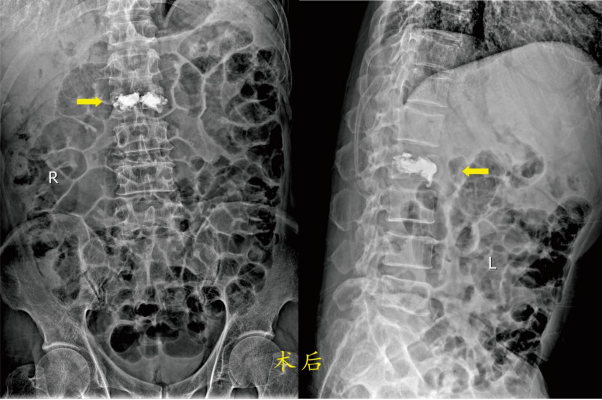

患者2:龚某某,男,67岁,因“摔伤致腰部疼痛伴活动障碍1小时余”急诊以“腰2椎体骨折”收入骨科住院。入院诊断:1.腰椎骨折(腰2);2、慢性阻塞性肺病伴有急性加重;3、肺气肿合并肺大泡;4、腔隙性脑梗死;5、.高血压病2级(高危);6、左侧颈内动脉斑块;7、高脂血症;8、肝功能不全;9、高尿酸血症;10、右肾囊肿;11、前列腺钙化灶。 骨科医师经检查及评估后了解到患者既往有高血压病,同时患有慢性阻塞性肺病,常年使用吸入药物治疗,在不吸氧时的血氧饱和度维持在90%左右,偶尔有胸闷气闭的感觉。

胸腰椎骨折的病人,术前需绝对卧床休息,长时间卧床的病人有坠积性肺炎的并发症风险,年龄越大风险越高。骨科医师向患者及家属讲解病情和治疗方法(微创手术或保守治疗即卧床休息)后,经过骨科团队讨论研究,决定为两位患者同样实施微创手术治疗:经皮穿刺椎体成形术。经过术前制定全面的手术方案,在手术室的全力配合下均顺利完成了手术。